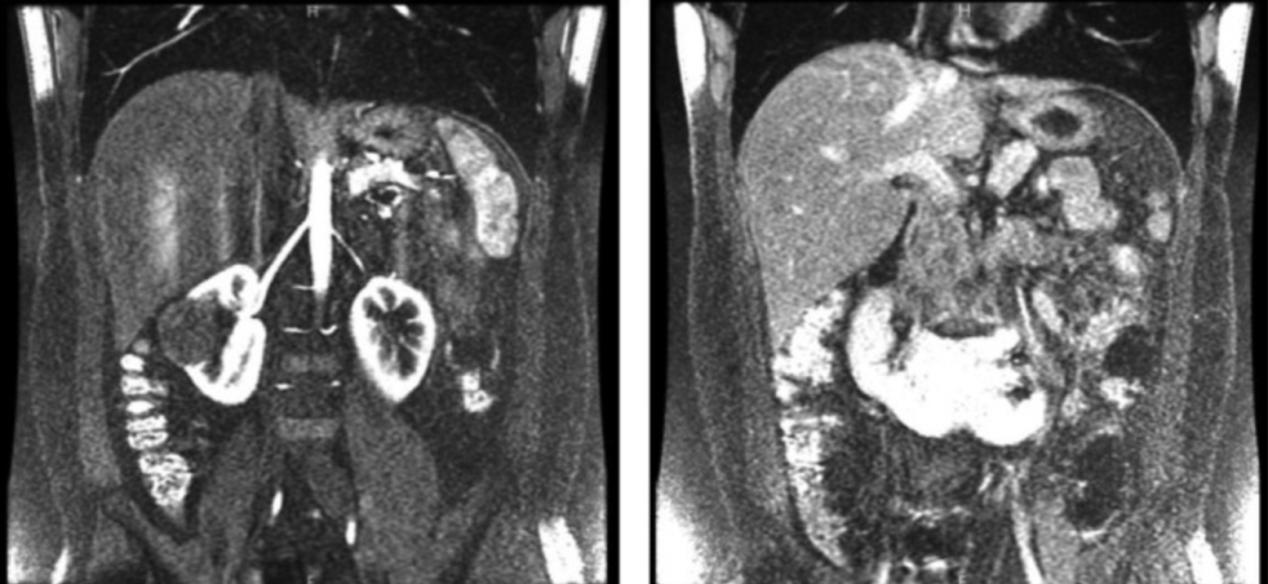

肾脏超声检查结果显示一个清晰的圆形异回声固体肿物(52 × 51 mm),在右肾中极向肾外延伸 (103mm),压迫肾窦。左肾旋转不良,位于正常解剖部位的尾部(图1)。随后,腹部和骨盆螺旋计算机断层扫描(CT)和腹部磁共振成像(MRI)显示 右肾中极50× 53 × 48 mm肿物,影响邻近右肝叶的肾盂输尿管系统,提示肾细胞癌(RCC),以及左输尿管近端一4mm结石,距离HK左侧肾盂输尿管连接处21mm(图2和3)。肾结石类型为草酸钙。在此之前,患者没有意识到自己的肾脏异常,也没有观察到任何泌尿系统相关症状。

图2 磁共振成像显示右中极马蹄肾及肿物,邻近右肝叶